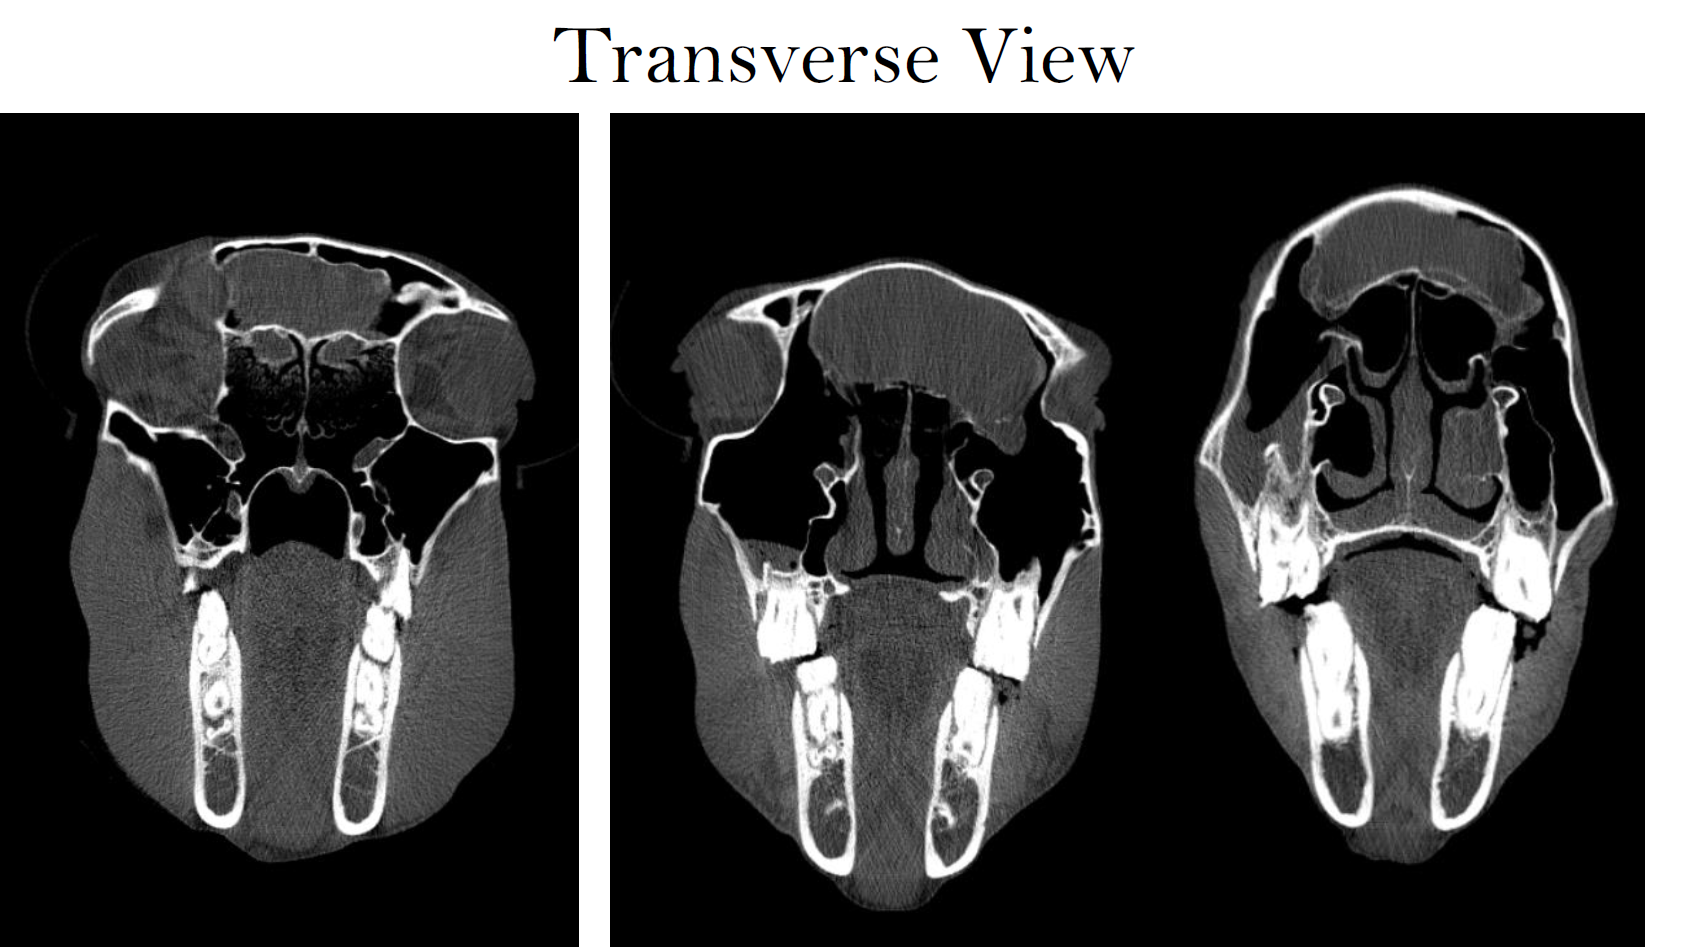

Case Example: 2‑Month‑Old Quarter Horse Colt, UMN Leatherdale Equine Center

The colt was discovered 36 hours after a suspected halter-related trauma with mild right head tilt, intermittent depression, and swelling over the left cranial neck and head.

On referral, the colt was bright and neurologically appropriate. Examination revealed mild head tilt, palpable crepitus over suspected fracture area, normal gait at walk and trot, and no overt neurologic deficits. CT was performed to evaluate suspected cervical fracture.

CT Findings

• CT identified fractures of the right jugular process and the right lamina of C1, with an open C1 fracture allowing a small amount of gas to enter the vertebral canal.

• Fragment displacement caused moderate canal narrowing at C1–C2 and subluxation of the right atlanto‑occipital joints.

• Soft tissue within the vertebral canal suggested hemorrhage or inflammatory debris, and mild spinal cord compression was suspected.

The CT findings provided definitive localization and severity grading, guiding further decision-making regarding stabilization, prognosis, and monitoring.